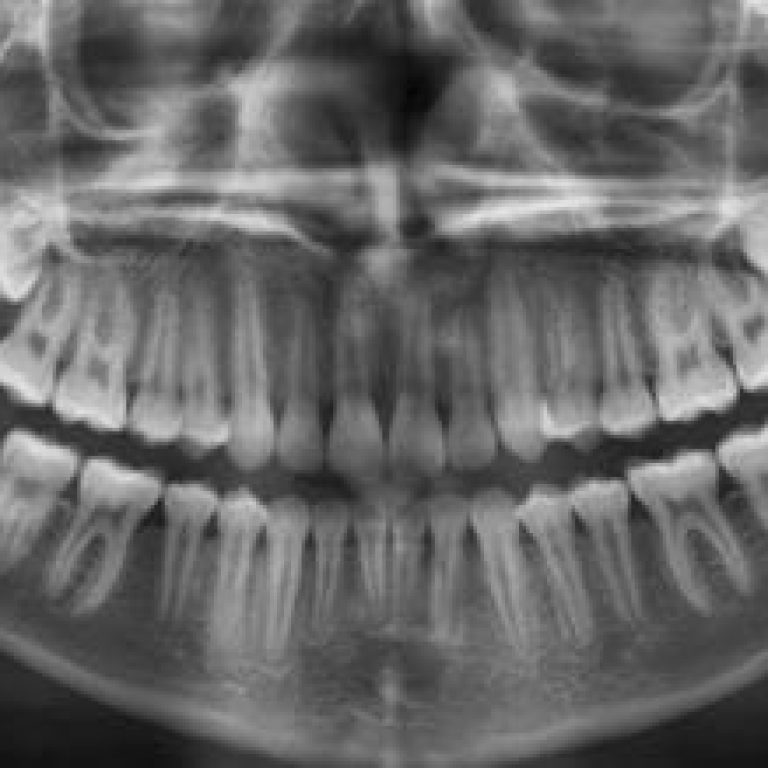

Malocluzia reprezinta o aliniere incorecta a dintilor in momentul muscaturii. In mod ideal, dintii de pe arcada superioara …